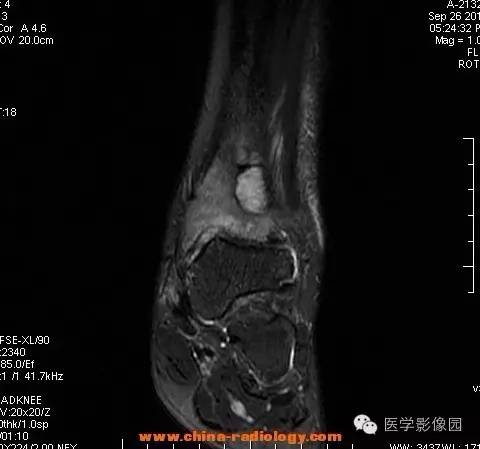

影像学表现:胫骨中下段干骺端不未规则形长T1长T2信号,T2WI见不完整环形稍低信号影,T2脂肪抑制低信号更明显,并见胫骨下段及踝关节后外侧软组织呈弥漫稍高信号,增强明显不均匀强化,增强见低信号环内有环形强化影。

影像学表现:表现为长骨干骺端有椭圆形密度减低区,边缘有清晰的骨质硬化,病变与邻近正常骨髓腔境界清楚。MRI上T1WI呈低信号,少数呈等信号,T2WI多为混杂高信号,增强扫描可见环状强化,强化的脓肿壁薄而均匀。